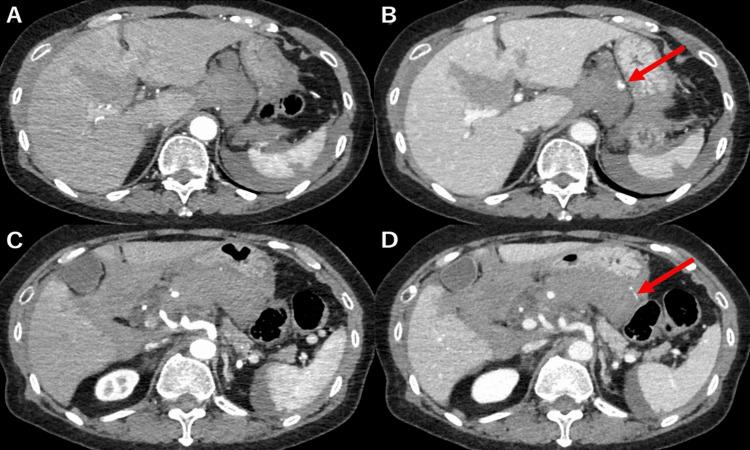

Gastric artery injury resulting from blunt abdominal trauma is rare, with only eight previous cases documented in the published literature. Our report describes a case involving an injury to the right gastric artery with concomitant injuries to the liver and spleen, for which arterial embolization targeting the right gastric artery was performed. The patient, a 66-year-old woman without any remarkable medical history, was involved in a motor vehicle accident. She was brought to the hospital in a state of shock and complaining of upper abdominal pain. Contrast-enhanced CT indicated hepatic and splenic injuries, intra-abdominal hemorrhaging, and effusion of contrast medium, suggesting involvement of the right gastric artery. Subsequent angiography confirmed irregularities in the diameter of the right gastric artery, prompting coil embolization. A conservative therapeutic approach was selected due to the absence of evidence regarding active hemorrhage or vascular injury within the hepatic or splenic regions. The patient remained clinically stable following the embolization, without any sequelae. Arterial embolization is warranted if preoperative contrast CT indicates signs of hemorrhage, even if hemostasis is ostensibly attained during angiography. Our findings allude to the feasibility of non-operative management (NOM) rather than laparotomy for cases of gastric artery injury.

钝性腹部创伤导致的胃动脉损伤较为罕见,既往发表的文献中仅记录了8例。我们的报告描述了1例涉及右胃动脉损伤并伴有肝脾损伤的病例,针对该病例对右胃动脉进行了动脉栓塞治疗。患者为一名66岁女性,无任何显著病史,遭遇了机动车事故。她被送至医院时处于休克状态,主诉上腹部疼痛。增强CT显示肝脾损伤、腹腔内出血以及造影剂渗出,提示右胃动脉受累。随后的血管造影证实右胃动脉直径不规则,遂进行弹簧圈栓塞。由于没有证据表明肝脾区域存在活动性出血或血管损伤,选择了保守治疗方法。栓塞术后患者临床情况稳定,无任何后遗症。如果术前增强CT显示出血迹象,即使在血管造影时表面上已实现止血,也有必要进行动脉栓塞。我们的研究结果表明,对于胃动脉损伤病例,非手术治疗(NOM)而非剖腹手术是可行的。